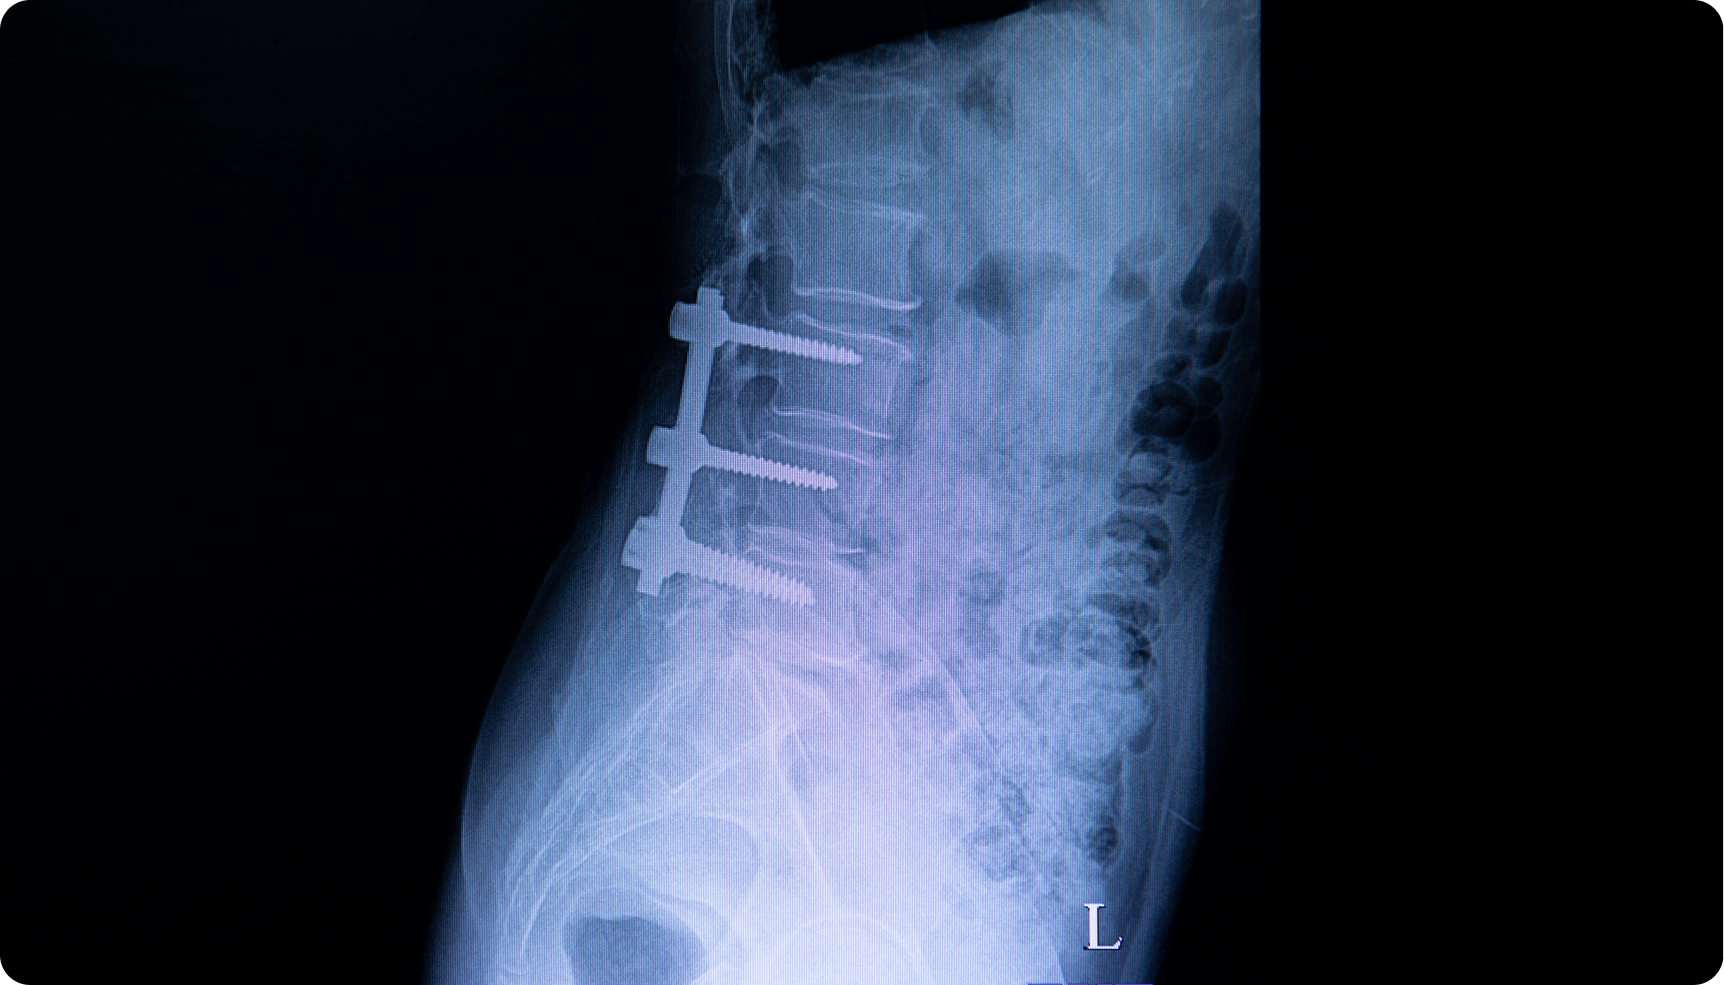

Prior spine surgery altering load on the SI joint

Answer: Adjacent levels often wear out faster.

Spinal fusion stabilizes one level but transfers stress to the discs and joints above and below, leading to adjacent segment disease. Scar tissue, muscle atrophy, and nerve irritation can also persist. Nonsurgical options like PRP or radiofrequency treatment can help preserve the surrounding spine.

Lumbar | Post-Surgery | Interventional Spine

Answer: They mean nearby levels or implants break down over time.

After fusion, joints next to the fused area compensate by moving more, sometimes developing arthritis or stress fractures. Hardware fatigue or loosening can also occur years later. Regular imaging helps detect changes early; pain-management injections or strengthening programs can often delay revision surgery.